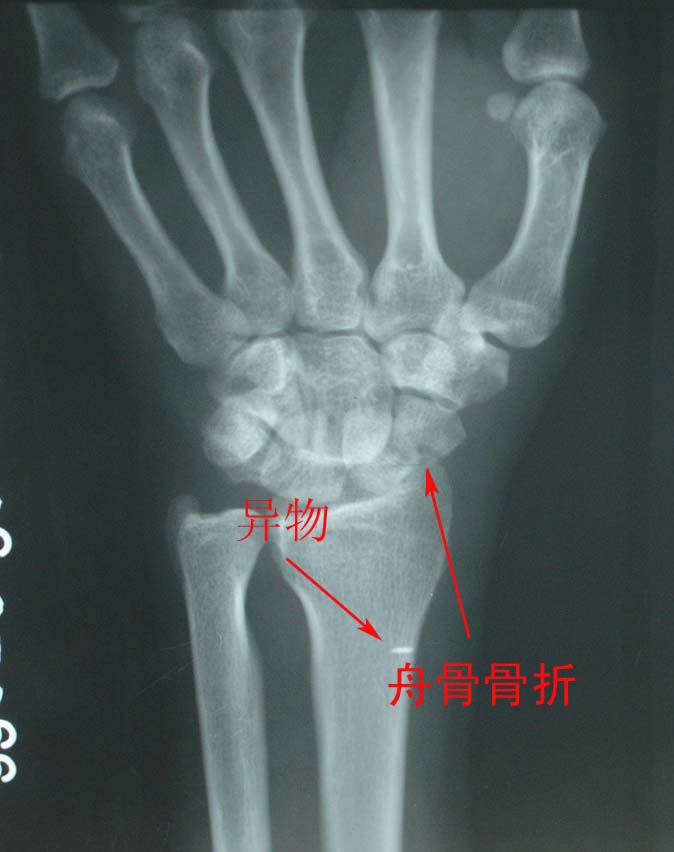

男,36岁,外伤后左腕部肿痛2小时。

考虑:1、左舟骨骨折;

2、月骨半脱位;

3、软组织内金属异物。

此例我感觉是“经舟骨月骨周围脱位”,我曾发布过一例,如下图:

我赞同是1、“经舟骨月骨周围脱位”,表现为月骨周围脱位拌舟骨骨折,且骨折远段随头骨向后脱位,而骨折近段与桡骨、月骨关系保持正常。2、软组织内金属异物。